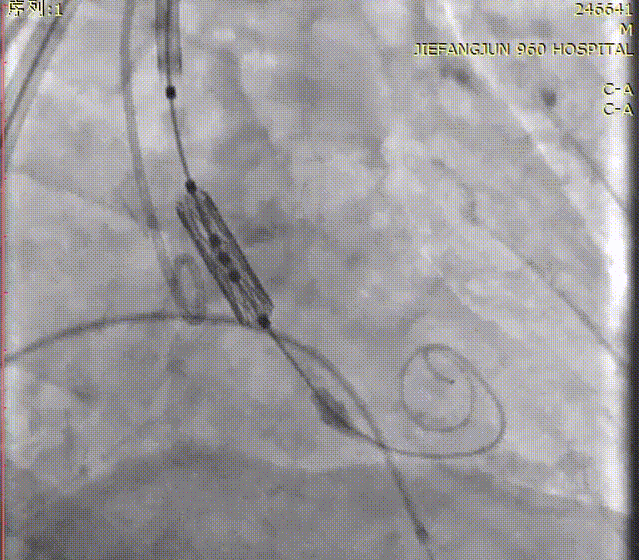

球囊预扩

随后,沿加硬导丝送入体外预装好的Prizvalve® THV 26瓣膜,顺利过弓跨瓣,精准定位后,以180次/分快速起搏,待收缩压降到50mmHg时,1-9定位、减容2.5mL策略进行释放瓣膜。

瓣膜定位造影

瓣膜释放后造影